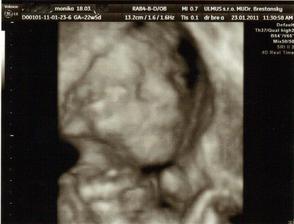

✿♥♥♥♥Bude to dievčatko!!!!! ♥♥♥♥✿

Bude to Stella 🙂

krasne 3D sono 🙂